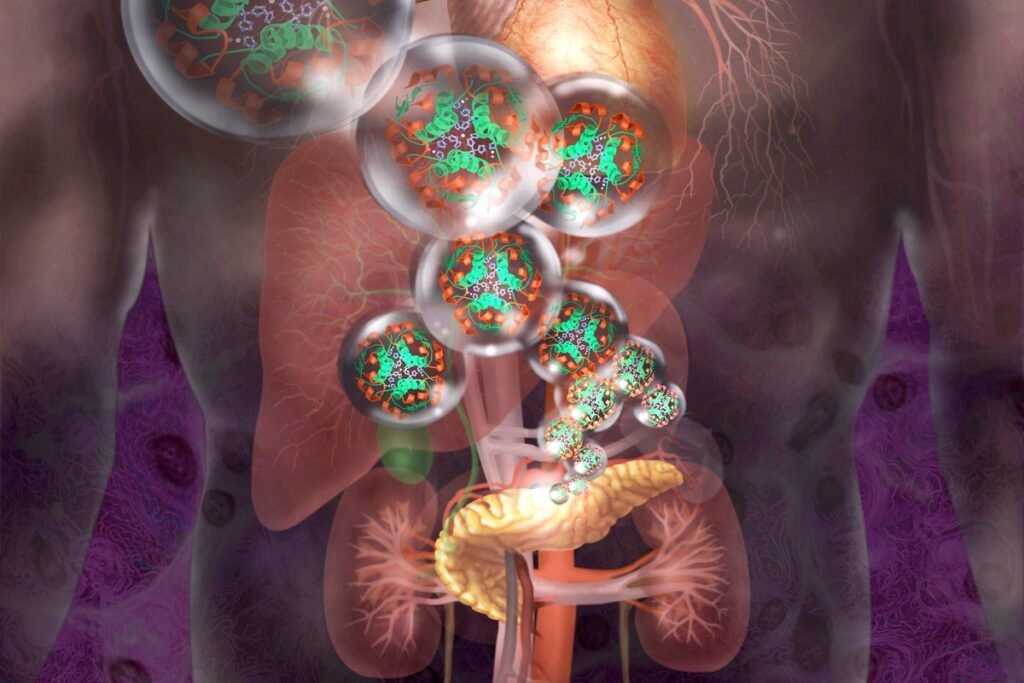

Insulin-producing cells can be genetically modified to hide from the immune system.

Jim Dowdalls/Science Source